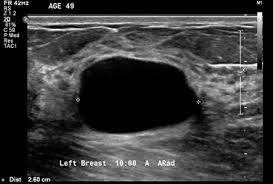

Kistler basit ve komplike kistler olarak iki ayrı grupta incelenebilir. Basit kistler kanser oluşturmazlar. Kistlerin içerisinde kitle olması, perdeli olması, duvarının kalın olması seyrek de olsa kanserle ilişkili olabilir.

Büyük kistlerin içindeki sıvılar iğneyle boşaltılabilir. Basit kistler bu işlemle tamamen kaybolurlar. İçi boşaltılıp da kaybolmayan kistler veya komplike kistler takip edilirler. Tanı için en basit ve etkili yöntem ultrasonografidir. Seyrek olarak MRI’a ihtiyaç duyulur.